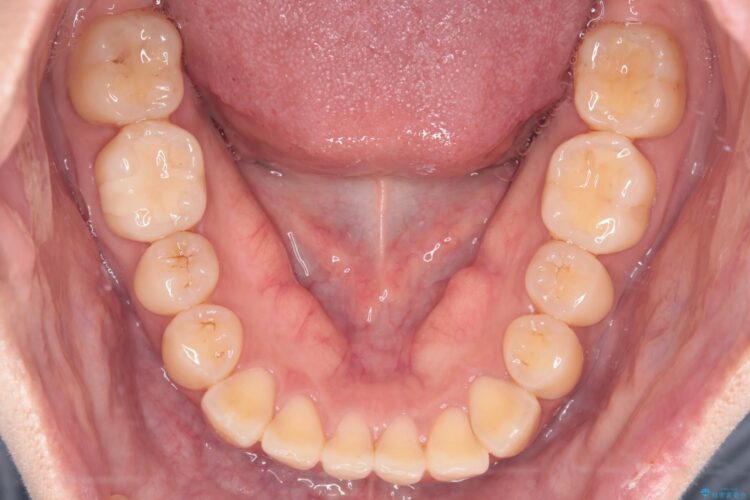

前歯の捻れとがたつきを改善するために、IPR(歯と歯の間を削る処置)と歯列拡大をすることで歯並びを整えていく治療計画を立てました。

かみ合わせを整えるためにゴム掛けも併用して治療を行いました。